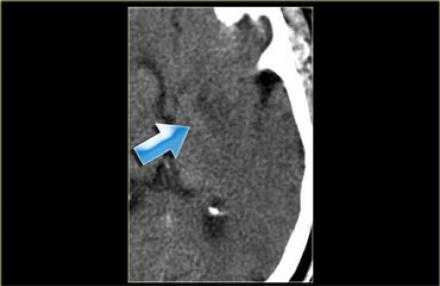

В данном случае признаки инфаркта едва уловимые. Гиподенсная зона в островковой области справа. В данном случае эти изменения соответствуют инфаркту, но у пожилых пациентов с лейкоэнцефалопатией тяжело отдифференцировать эти две разные патологии.

Вышележащие изображения — КТ-ангиография. После выполнения КТА — диагноз инфаркта в области СМА, как на ладоне.